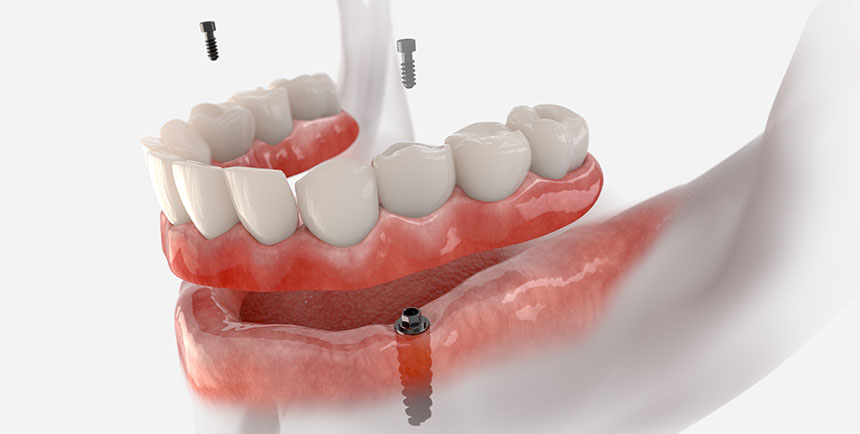

Pre Prosthetic Surgeries

At Palanpur Dental – Astha Multi Speciality Dental Clinic, under the expert guidance of Dr. Motilal Agrawal and Dr. Chintan Agrawal, we provide comprehensive pre-prosthetic surgical procedures to ensure the success and comfort of dentures, crowns, bridges, and dental implants.

• Advanced implant procedures like sinus lifts, nerve repositioning, and ridge augmentation for complex dental implant cases.